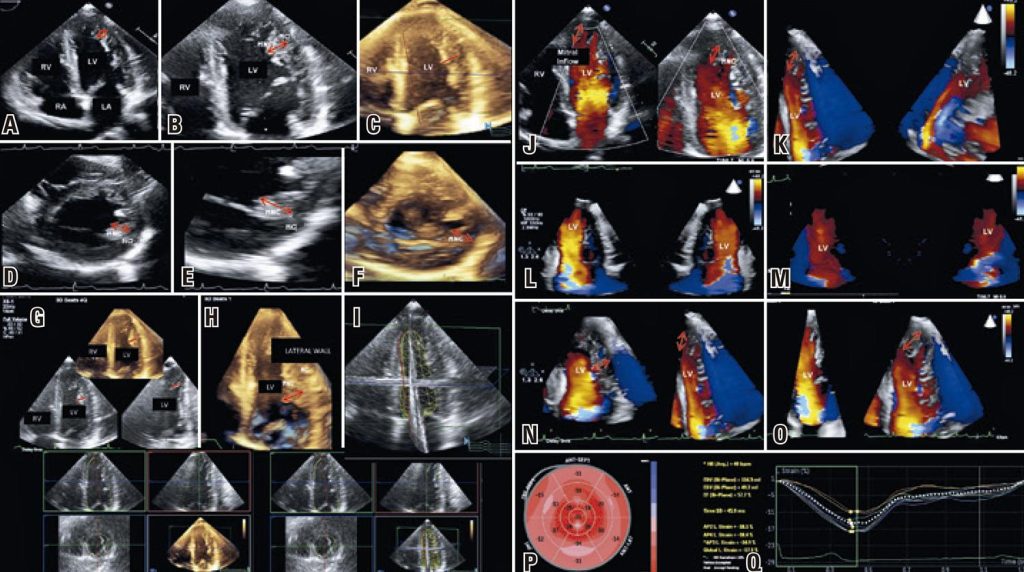

Left ventricular noncompaction highlighted by three-dimensional and speckle tracking echocardiography

Left ventricular noncompaction (LVNC) is a relatively new and heterogeneous cardiomyopathy, first reported by Chin et al. in 1990.() It is characterized by prominent ventricular trabeculations, intratrabecular recesses and a bi-layered myocardium, composed of compacted and noncompacted layers.(,) Left ventricular noncompaction may be an isolated finding or associated to other cardiomyopathies, metabolic disorders and congenital heart diseases.() It is believed to result from failure of ventricular compaction in the embryogenic phase, with increasing evidence of a genetic component.()

Since its first description, much has been learned about this disease, but there are some limitations for its diagnosis. Cardiac magnetic resonance imaging is considered the gold standard for diagnosis of LVNC, but echocardiography remains the first line imaging modality due to its availability and cost-effectiveness.